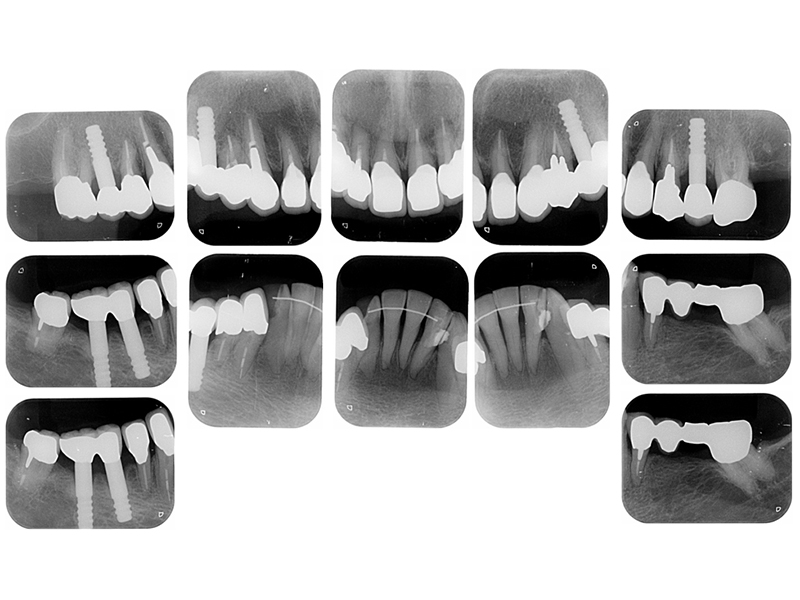

治療終了時

before

after